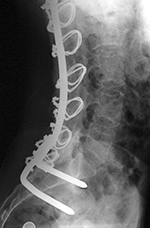

| Lumbar spine bony disk strut, pedicle screws, and pedicle rods (AP view) |

Lumbar spine bony disk strut, pedicle screws, and pedicle rods (lateral view) |

| There is an anterior allograft bone strut used to treat metastatic neuroblastoma in the L4 vertebral body. The bone strut crosses both the pathologic vertebral body as well as its adjacent disk. The anterior position of the bone strut is typical for these struts. From Hunter, 2004 |